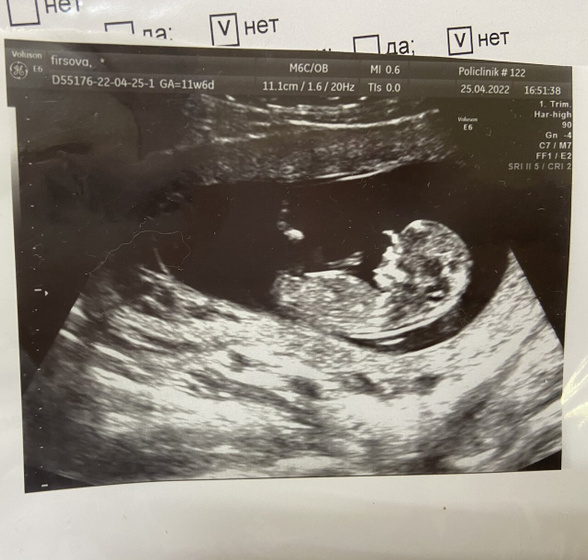

Знаю что по такому фото не понять, просто интересны предположения, мальчик или девочка?) это скрининг в жк в 11 недель, скоро на платный, он в 13 будет

Та часть где это видно на фото засвечено. У меня на фото в 12,2 прям видно было эту косточку. И она смотрела вперед. Это значит девочка, но мне и сказали что девочка.

Мне на скрининге в 12 недели сказали предположительно девочка, по факту с 16 недель парень)) поэтому не обнадеживайте себя, сделайте УЗИ в 16 недель, там уже различия визуально видно лучше)